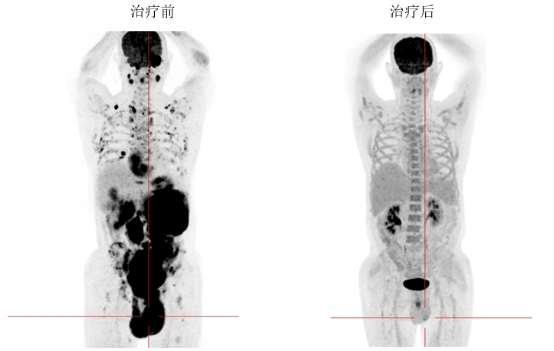

2025 年 5 月,唐先生因「左侧阴囊肿大 4 个多月」来到和祐医院就诊。经全面检查,他被确诊为「弥漫大 B 细胞淋巴瘤」,且病情已进展到极其严重的阶段。PET-CT 显示肿瘤已「全身广泛转移」——鼻咽颅底、甲状腺、心包、胸壁、胆囊、胃、肾上腺、前列腺、双侧精囊腺、尿道球部、双肾及双侧输尿管周围、双侧睾丸、腹膜、骶前筋膜、腹壁皮下;并有全身弥漫多发骨质破坏及多发增大淋巴结,骨髓细胞学检查提示:原始细胞占比 83.25%,还合并高血压、糖尿病、消化道出血等多种基础疾病,情况十分危急。